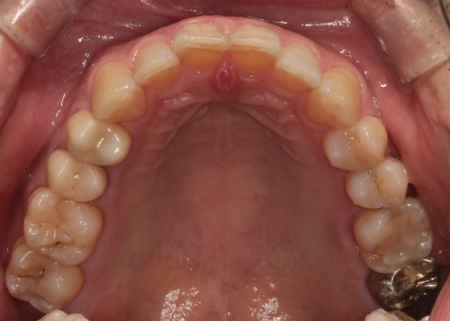

治療後

完成した被せ物はネジで固定するスクリューリテインという方法を採用してしっかりと取り付け、噛み合わせに問題がないことを確認して、治療を終了しました。